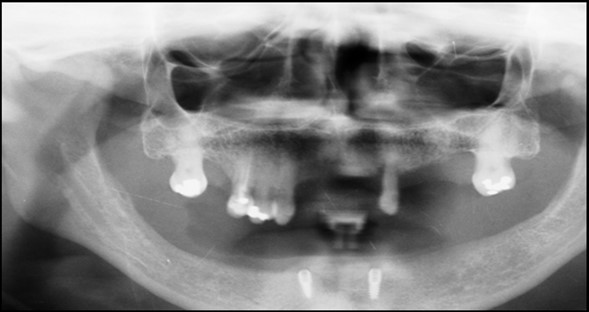

Figure 6.Panoramic radiograph after the insertion of two implants

General criteria for survival and success of implants have been used to evaluate the efficacy of immediately loading mandibular implants. For example, survival criteria include how the implant performs, particularly regarding the absence of pain, infection, and paresthesia. Implant immobility and the absence of periimplant radiolucency under radiography are 2 more criteria of implant survivability.6, 7 Success criteria include the additional element of absence of vertical bone loss; specifically, less than 1 mm during the first year and less than 0.2 mm annually thereafter. Granted that success rates for immediatel oading of implants in the edentulous mandible are not as high as rates for the traditional 2-stage approach, conditions nevertheless often warrant the 1-stage surgical option described here.7, 8, 9 (Figure 12).

In conclusion, within the limits of this interim report, immediate loading of two-implants supporting a locator retained mandibular overdenture seems to be a suitable treatment option. The marginal bone level changes around immediately loaded implants are comparable to those seen around implants loaded with a torque do not effect peri-implant bone loss. Implant survival of immediately loaded implants may be lower than those loaded with a delayed protocol, but this needs to be confirmed in future investigations with a larger sample size. Elayed protocol, at 6 months postsurgery. Implant length and peak insertion.